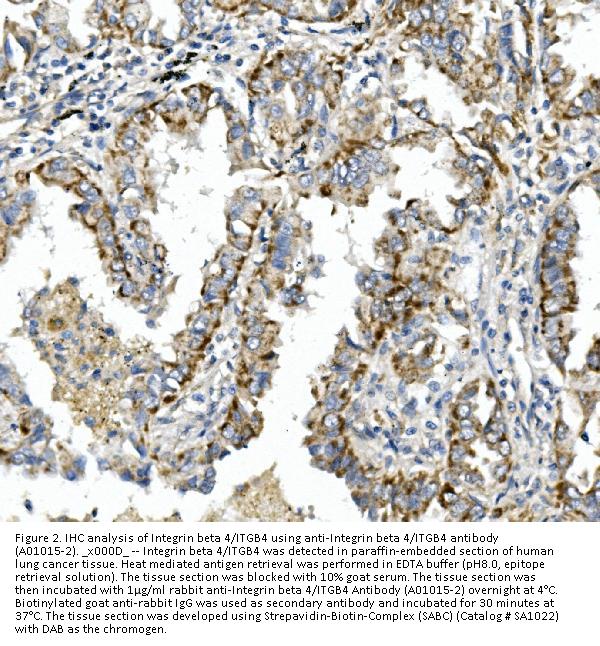

Immunohistochemistry (Paraffin-embedded Section), 0.5-1μg/ml, Human